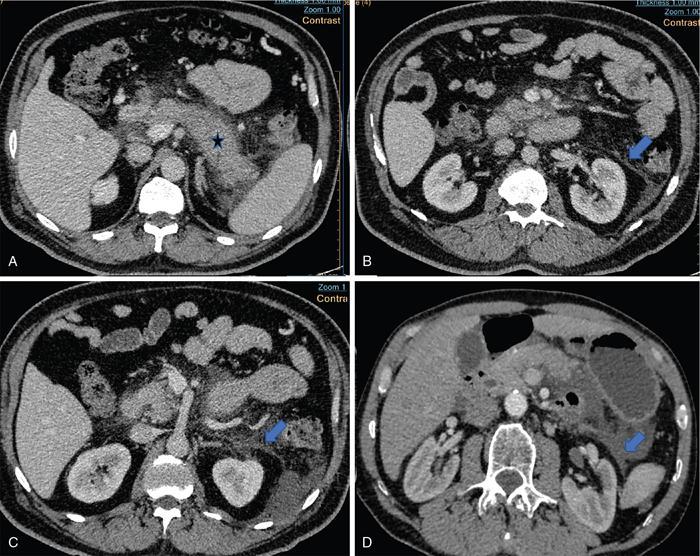

Fig. 10.17.1.3 Contrast-enhanced axial CT sections in a case of acute pancreatitis (asterisk in A); the pancreas appears diffusely bulky with peripancreatic fat stranding. Thickening of the anterior renal fascia (blue arrows in B and C) with fluid collection in the anterior pararenal space (blue arrow in D).

Image

Fig. 10.17.1.4 Contrast-enhanced axial and sagittal CT sections in a case of acute right pyelonephritis (A and B); the right kidney appears bulky with perinephric fat stranding. Thickening of the perinephric bridging septae (blue arrows in A and B) and posterior renal fascia. Axial T1W and axial STIR images also depict the thickened perinephric bridging septae (blue arrows in C and D).

Fig. 10.17.1.5 Contrast-enhanced axial CT sections in a case of acute right pyelonephritis (A–D); the right kidney appears bulky with perinephric fat stranding (asterisk in A). Thickening of the posterior renal fascia (blue arrow in A) and perinephric bridging septae (blue arrow in B). The inflammation extends into the right iliac fossa via the inferior cone of the perirenal space, in contact with the psoas major muscle (blue arrows in C and D).